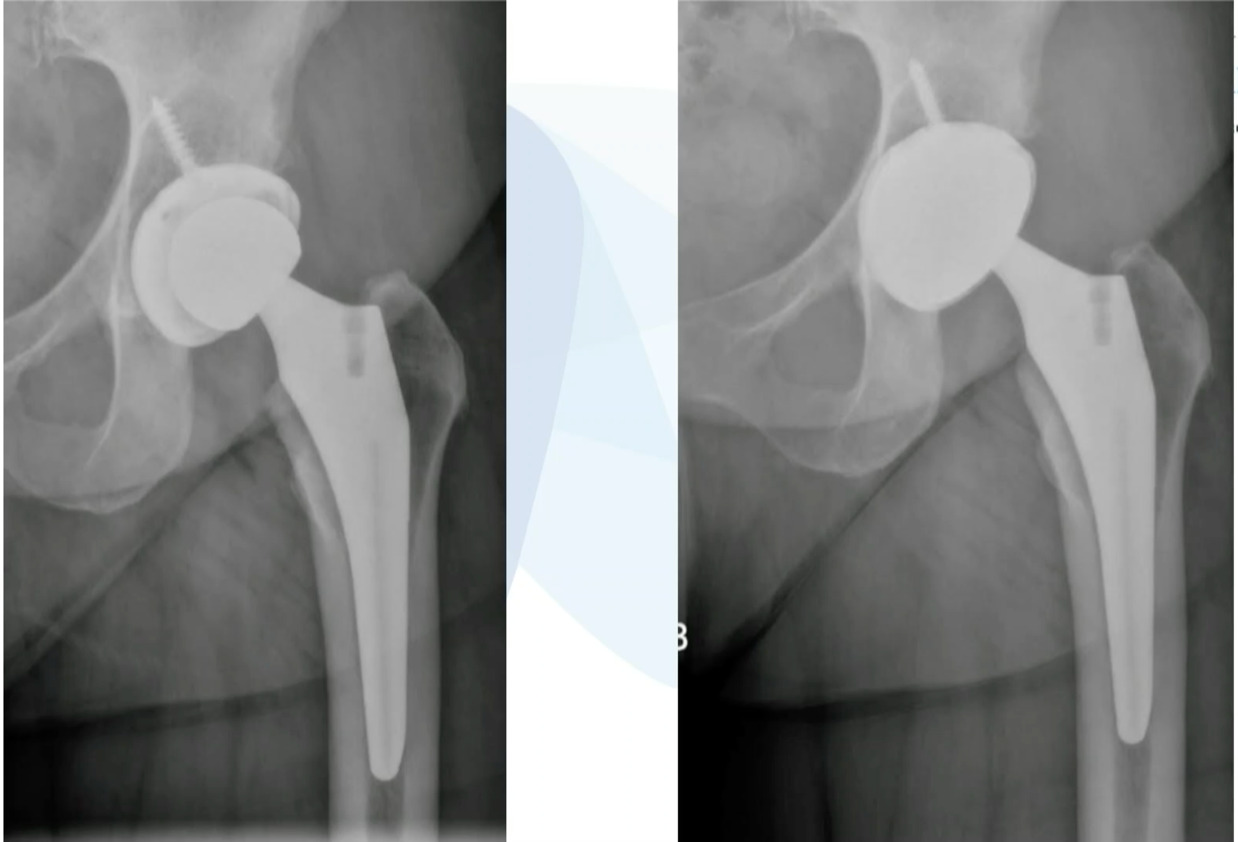

It’s just a couple quick cases that I feel are pretty ideal for the ASC. This is just a loose femoral stem here went in and actually revise this with a modern triple tapered stem. (Figure 4)

We’ve done this on quite a few cases and this is working really well, but you don’t have to use a primary stem, you can use a revision stem. But these loose components are ideal for the ASC setting. This was an ileus-psoas impingement. (Figure 5)